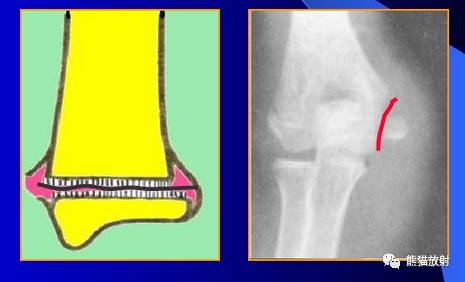

Salter-Harris II型:骨折累及骺板及干骺端,骨骺骨折中最多见(75%),预后较差。

第二型(Ⅱ型) 骨骺分离伴干骺端骨折。该型损伤最多见,占骨骺损伤的48.2%,好发部位在桡骨远端、肱骨近端及胫骨远端。多发生在10一16岁的儿童,骨折线通过肥大并累及干骺端的一部分,骨折片呈三角形,在骨折端成角之凸侧有骨膜撕裂,而凹侧骨膜完整、复位容易,预后良好。